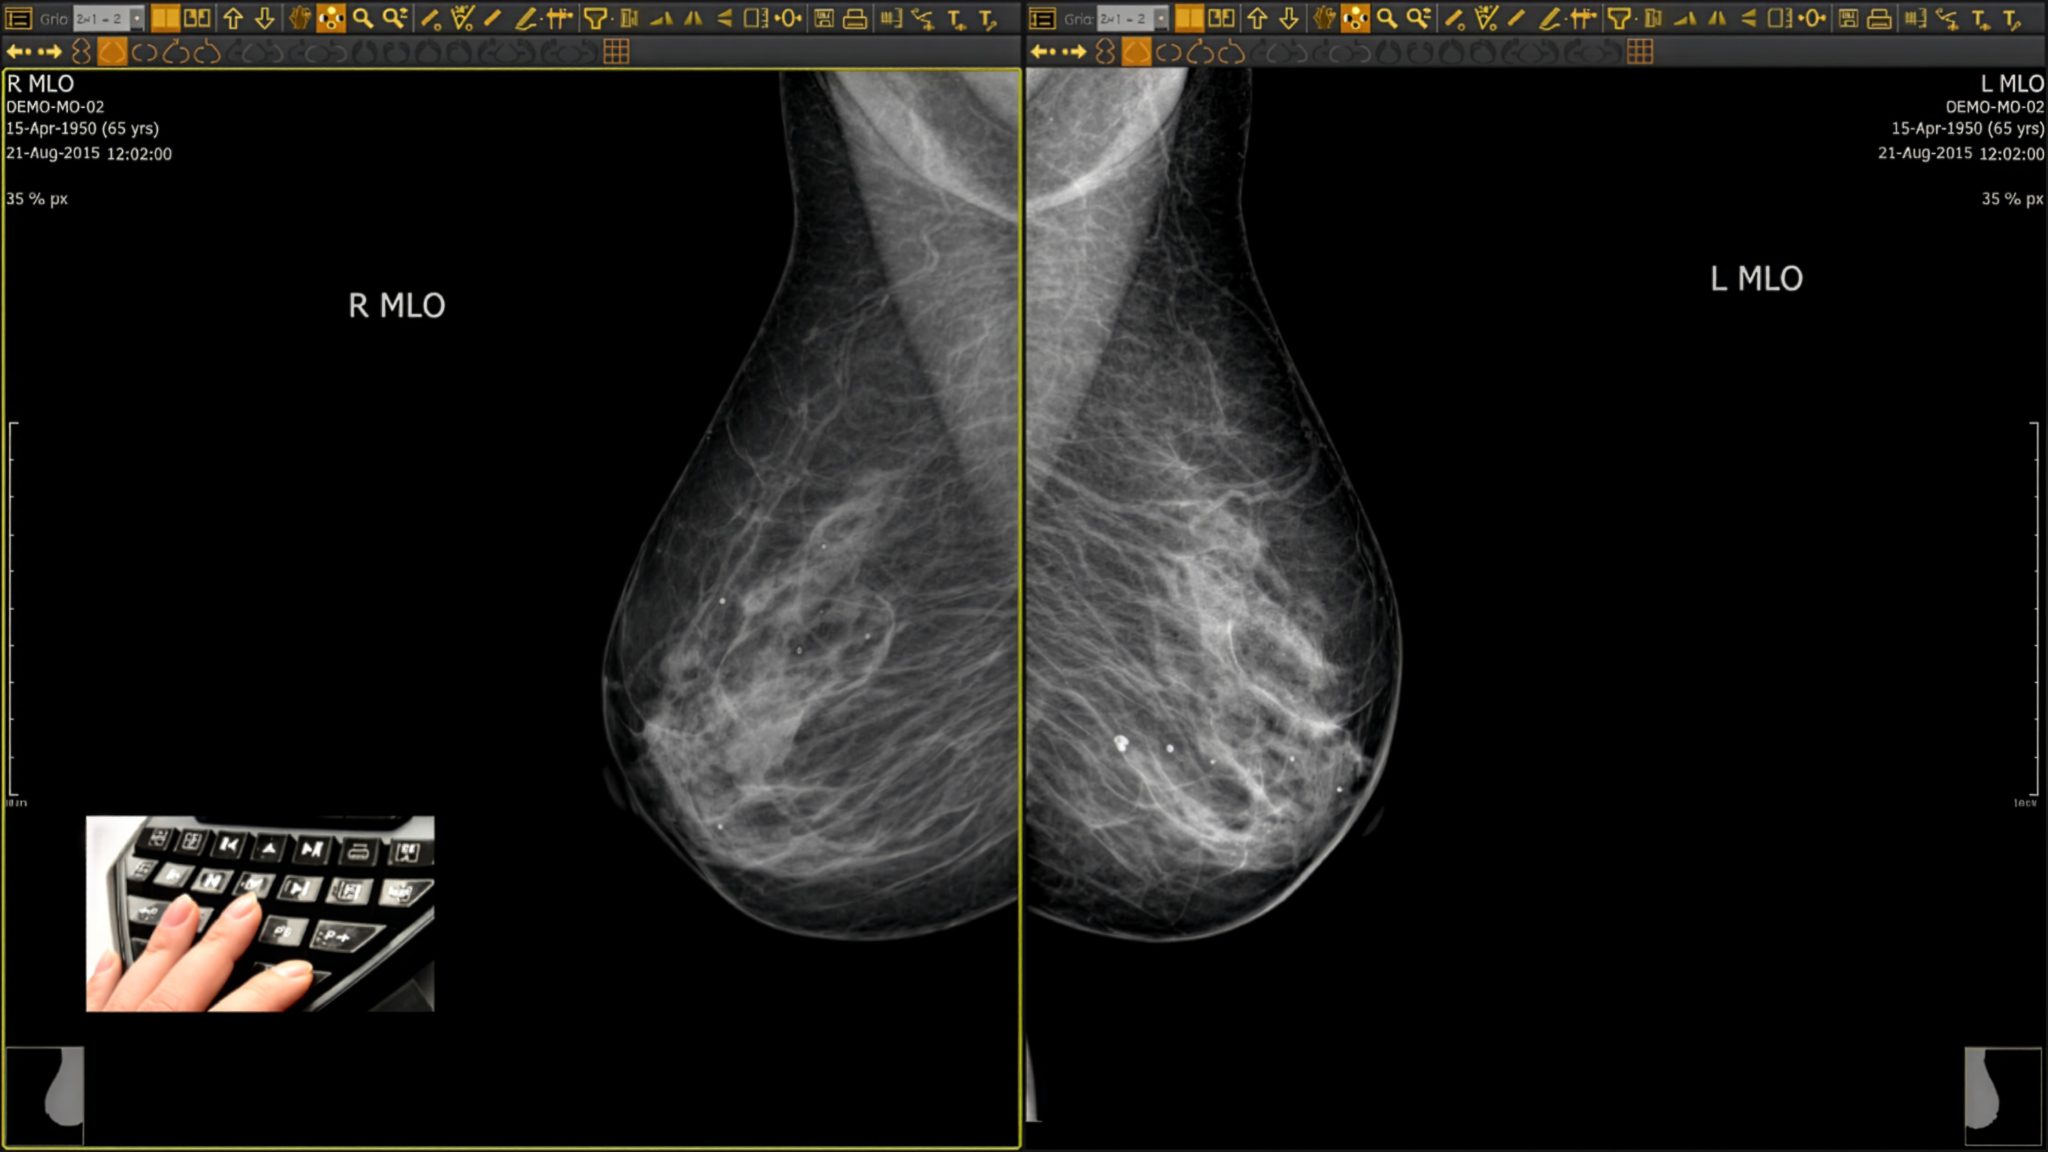

ÆSTIMAX

Una potente stazione di diagnostica mammografica multimodale che consente di eseguire lettura e refertazione, offrendo ai radiologi una vasta gamma di opzioni per la visualizzazione, l’analisi, il confronto, il trasferimento e l’archiviazione di immagini digitali, attraverso l’interfaccia DICOM. Dalla lettura alla diagnostica: un’unica stazione per illuminare ogni dettaglio.